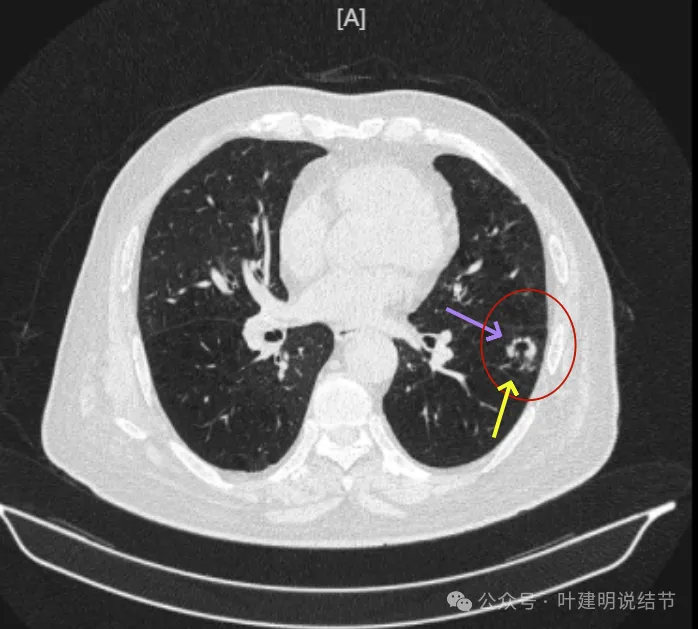

再看2024年9月时的影像:

病灶出现,紧贴叶间裂,有小血管走向病灶侧。

中间有空腔,叶裂侧实性并牵拉叶间裂。

囊腔灶、轮廓清、小血管进入囊壁、囊壁厚薄不均、叶间胸膜牵拉。

表面不平、混合密度、囊腔壁厚薄不均、内壁不光滑、有细支气管扩张通气征。

明显壁厚薄不均的囊腔灶,囊壁基本实性,表面不平,内壁不光滑,且邻近叶间裂并牵拉叶裂。